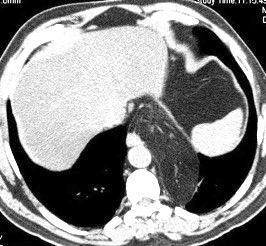

49. INVERSIÓN DIAFRAGMÁTIC. MESOTELIOMA

La ocupación del espacio pleural por derrame (o obstrucción aérea) se acomoda con expansión aumentada de la caja torácica, especialmente en eje vertical. La consecuencia es aplanamiento e incluso inversión diafragmática.

Afzal S, Fatima K, Ambareen M. Antenatal ultrasound diagnosis of congenital high airway obstruction syndrome: a case report and review of literature. Cureus. 2019. Thoma R et al. Physiology of breathlessness associated with pleural effusions. Curr Opin Pulm Med. 2015

Wang JS et al. Changes in pulmonary mechanics and gas exchange after thoracentesis on patients with inversion of a hemidiaphragm secondary to large pleural effusion . Chest 1995

Mesotelioma epitelioide